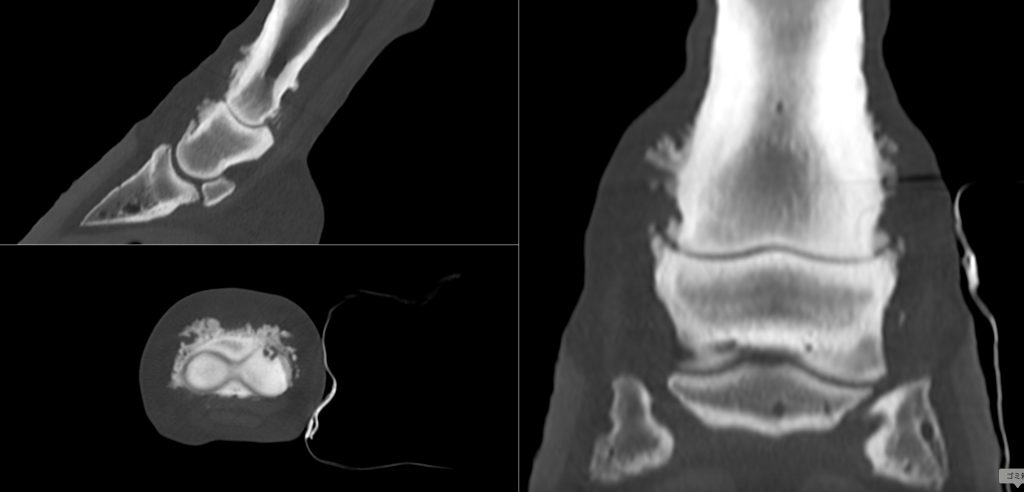

外科治療された繋関節症の馬

19歳の障害競技馬。 130cmクラスの競技にでていた能力のある馬でした。

2年ほど前から左前肢の跛行が徐々にはっきりとして、競技を引退していました。

触診と超音波検査で浅屈腱の外側枝に損傷がありました。

繋関節の固定には関節を開いて、関節軟骨を掻把して、関節が曲がらないようにプレートとスクリューで圧着する方法があります。(右図)

この馬は、来院した時点でかなり関節周囲に骨の増殖が起きており、肢も曲がらない状態に近かったので、より侵襲の少なく、早く関節固定できる手術方法を選択しました。